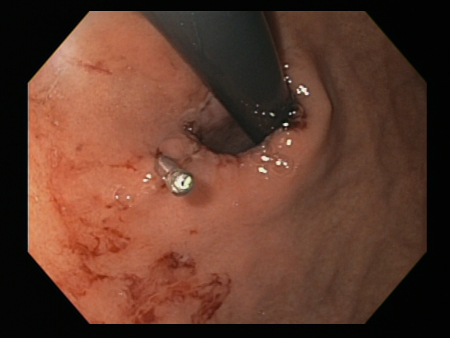

A through-the-scope clip deployed in the center of the lesion (no previous epinephrine was infused in this case)

From the collection of Juan Carlos Munoz, MD, University of Florida